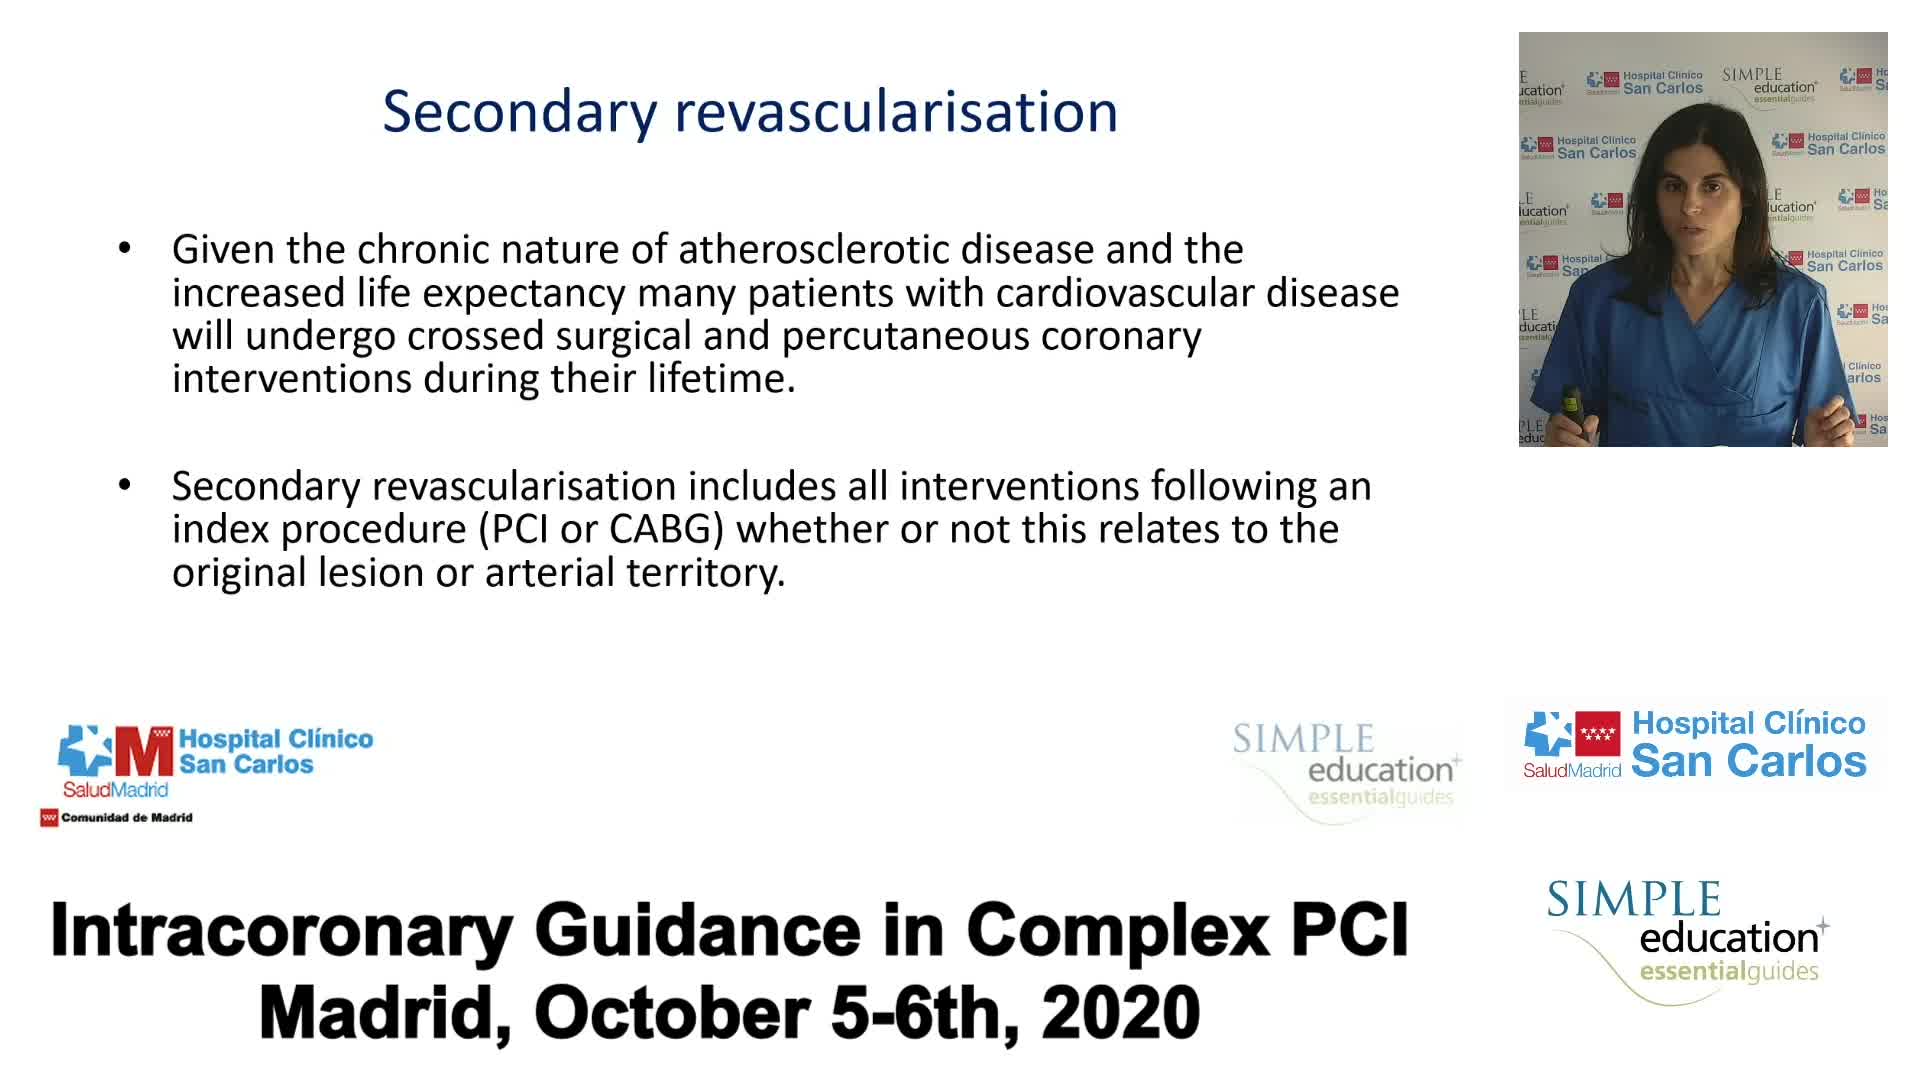

Revascularisation in stable angina: a contemporary perspective - Dr Rasha Al-Lamee